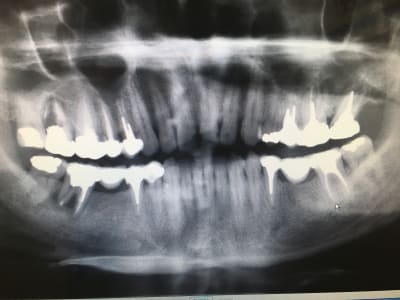

C'est rien ca, je te présente des travaux conforme aux tarifs de la grande sécurité sociale française d'un praticien qui gagne bien sa vie

Nb : le oatient venait car le bridge secteur 3 se casse la gueule : IC de 0.1 mm (sans blague), et couronne pas aux limites (qui sont de toute façon pas taillées)